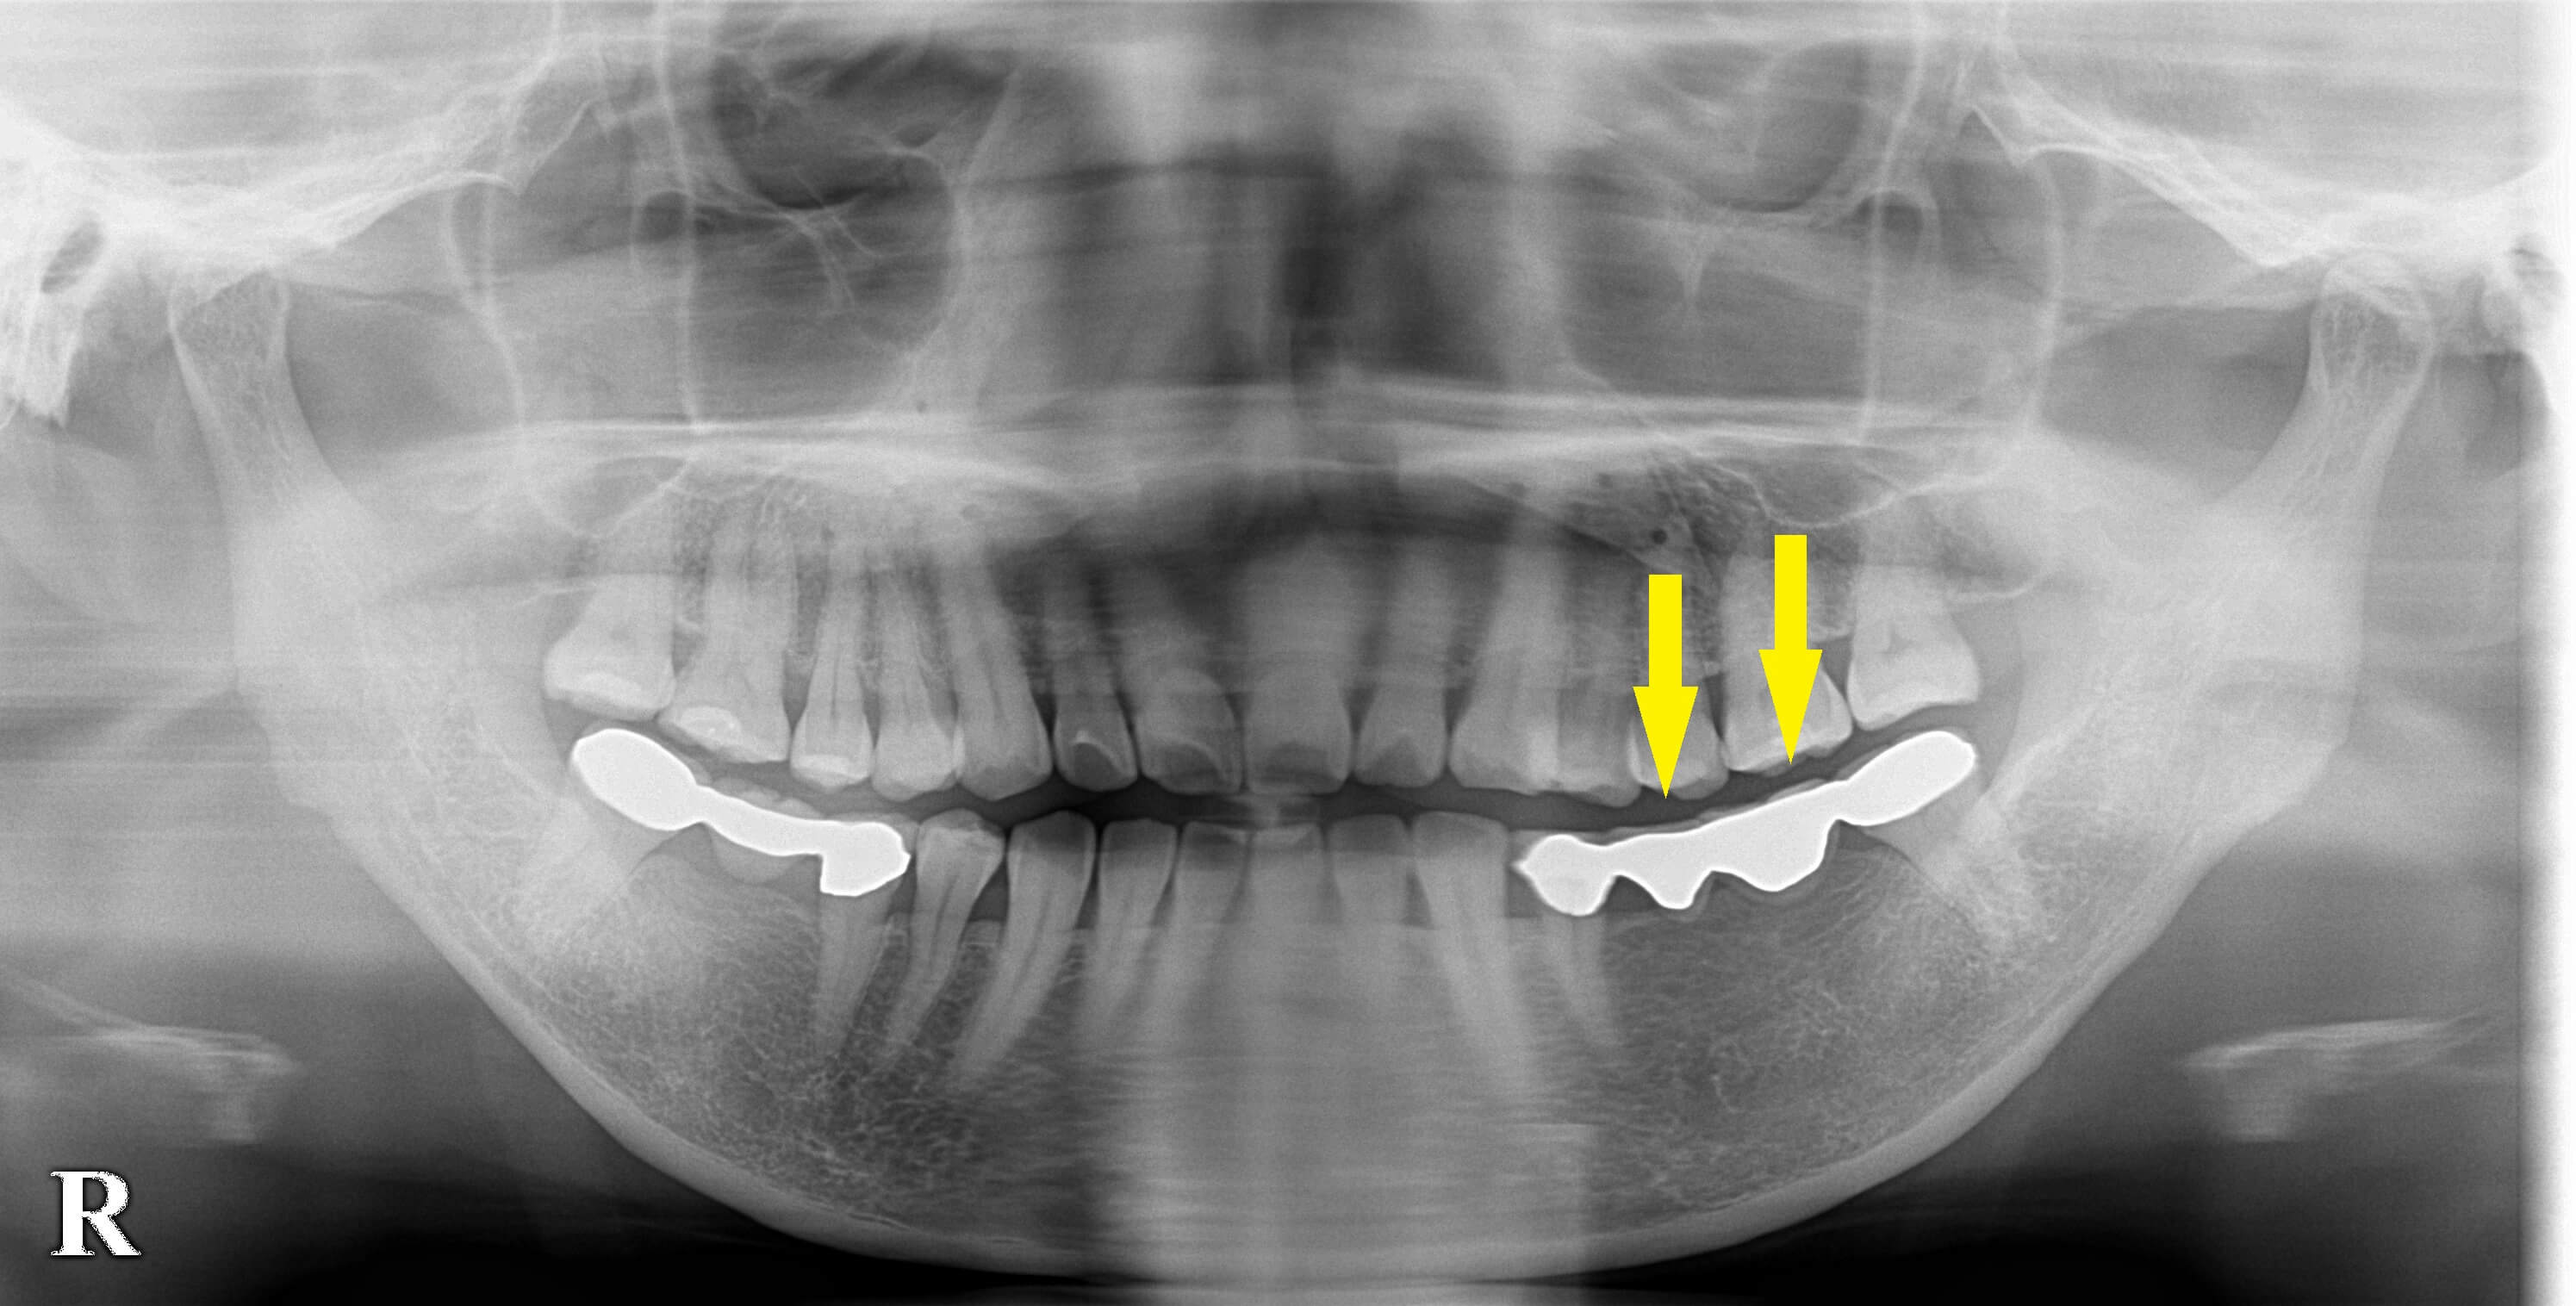

レントゲン、CTを撮影し、骨がかなり薄いことが判明しました。

骨の高さ、神経との距離は問題ありませんでしたので、骨をやや拡げる手技と骨幅の広いやや深めの位置にインプラントを埋入する方法で、手術を行いました。

下の写真、下段の写真左が手術前のCT、右が手術後のCTです。良好な状態で、インプラント埋入ができています。